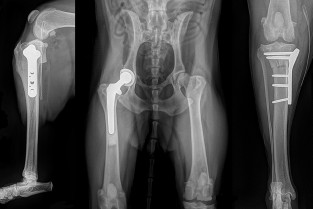

Traumatologie

- réaliser précisément l’examen orthopédique du grasset et de la hanche ;

- décrire les principales affections orthopédiques du grasset et de la hanche ;

- interpréter les examens d’imagerie du grasset et de la hanche

- proposer un traitement médical ou chirurgical adapté à l’affection diagnostiquée ;

- établir le pronostic fonctionnel du grasset et de la hanche après traitement.